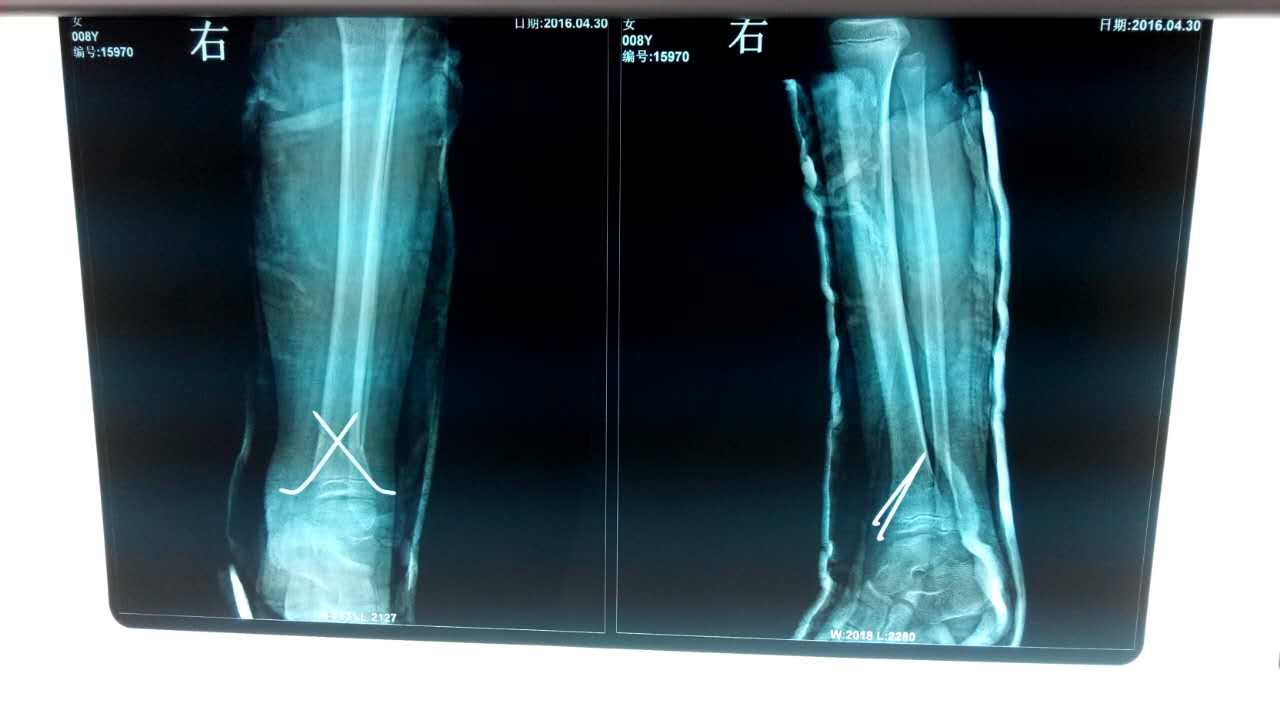

为了进一步贯彻执行省中医药管理局对骨伤科7种优势病种进行临床推广,进一步减轻病人负担,我院骨伤科自2014年12月份以来先后选派科内技术骨干分别到济南和文登正骨医院进修学习了经皮穿针内固定治疗锁骨骨折等7种优势病种的治疗方法并于近期在临床开展应用。2016年04月28日我院骨伤科在C型臂透视下成功完成了一例下肢胫腓骨双骨折病例,目前病人已康复出院。今后我们将继续开展此类手术。附病人手术前后X光片: